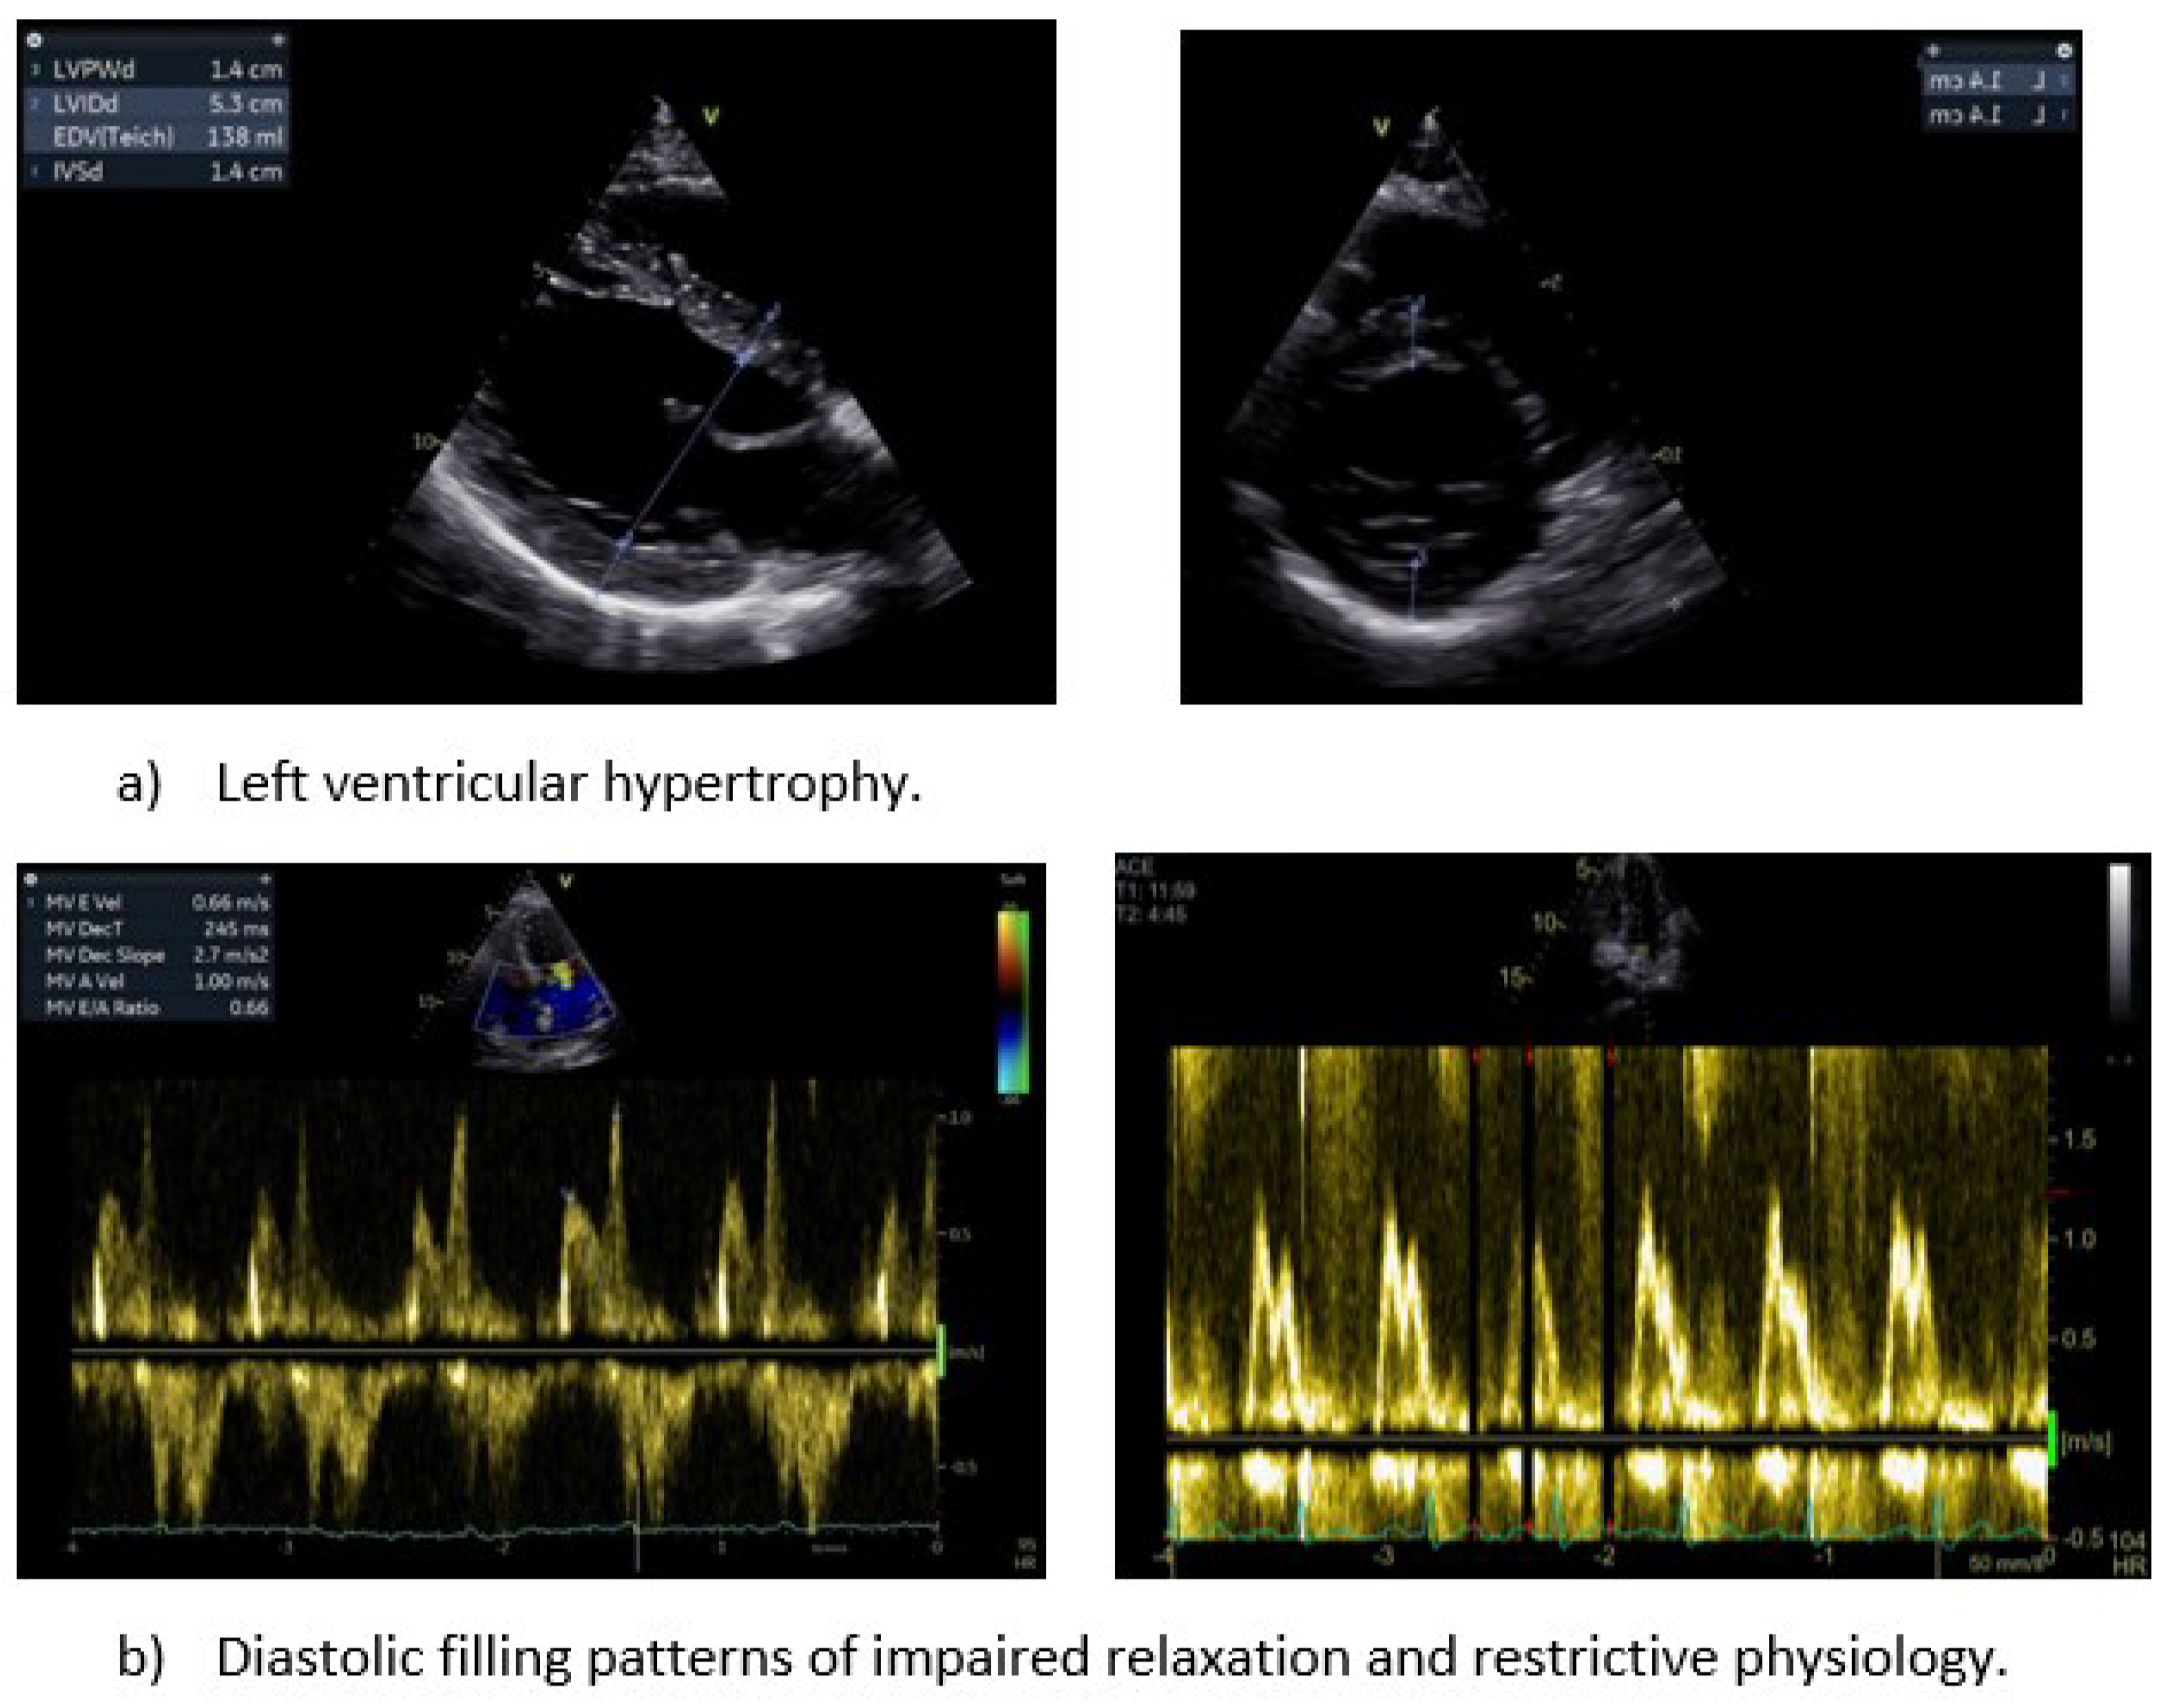

Figure 2. Classical echocardiographic indices of hypertensive heart disease.

Mitral inflow measurements play a crucial role in assessing diastolic function. Parameters such as, E and A velocity, their ratio (E/A), the deceleration time of E velocity, and the isovolumic relaxation time provide valuable insights. Notably, in hypertensive individuals, a normal in-treatment transmitral flow pattern serves as an indicator of a lower risk for HF, irrespective of BP levels. Although the implementation of antihypertensive therapy in patients with LVH improves mitral inflow patterns, this has not been correlated with a reduction in cardiovascular morbidity and mortality [57]. On the other hand, high E/A ratio has been associated with grade III diastolic dysfunction indicating high LV filling pressures and poor prognosis, especially when HF has been already developed [58,59].

The main limitation of echocardiography in diastolic dysfunction assessment is the clustering of numerous parameters and the inaccuracy in blood flow calculation. The proper alignment of the ultrasound beam is pivotal, given that Doppler tends to significantly underestimate flow velocities when the angle of interrogation exceeds 30°. To counteract the impact of transducer angulation, it is imperative to align the Doppler sample as parallel as possible with blood flow, ensuring optimal waveform morphology and maximal diastolic flow velocities. Color flow echocardiography may guide the alignment of sample volume parallel to flow [60]. The placement of pulsed-Doppler sample at the tips of the mitral leaflets (4 chamber view) is a prerequisite for the estimation of the left atrioventricular gradient, which may be miscalculated if it is placed at the mitral valve annulus level. Using the lowest filter setting is advised to capture the full velocity profile [61].

The pulsed Tissue Doppler-derived E′ velocity of the mitral annulus is an essential component in the evaluation of cardiac diastolic function. A decline in septal (<7cm/s) and lateral e' (<10cm/s) and the increased average ratio (E/e’ ≥14) signal compromised LV relaxation, albeit with certain limitations, like limited mitral annulus movement, calcification, or prosthetic valves (aortic or mitral). It is worth emphasizing the predictive capability of the E/E′ ratio for primary cardiac events in a hypertensive population without established cardiac disease [62]. The additional assessment of late (atrial) diastolic velocity (A′), may be influenced by LA function and LV end-diastolic pressure, but its diagnostic and prognostic values have not been established.

The evaluation of pulmonary venous flow pattern, when obtainable, has been implicated as an independent diagnostic criterion and a valid predictor of CVD events in essential hypertension. A high S/D ratio per se is independently associated with an increased cardiovascular disease risk in hypertensive patients [63]. Furthermore, the concomitant high pulmonary venous systolic-to-diastolic wave ratio (S/D, normal values: male < 1.51, female < 1.66) and a low E/A ratio exerts predictive value in HHD65. In TTE S, D flow data are usually acquired from the orifice of the right upper pulmonary vein in the apical 4-chamber view. Color flow Doppler should be employed to accurately place the sample volume 1 to 2 cm into the pulmonary vein, acknowledging that the far-field nature of the structure may limit the quality of the recording [64]. Overall, the echocardiographic assessment of diastolic function has several limitations, including dependence on number of Doppler measurements, potential interobserver variability and acoustic window challenges in hypertensive population. In contrast, CMR has the advantage of precise volumetric measurements, tissue velocity mapping, independent of acoustic window quality [65].